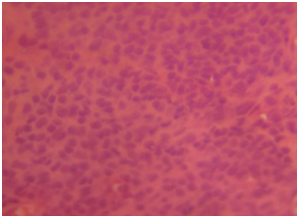

Gross specimen showed a rubbery grayish white tissue that was partly covered by an ellipse of skin and it measured 4.5x2x2 cm. The cut surface appeared solid grayish white. Histological sections showed skin tissue displaying monomorphic lymphoid cells focally arranged in a nodular pattern invading the dermis with numerous foci of epidermal infiltrations (Figure 3) (Figure 4). The cells are predominantly small and medium sizes with an occasional blast and they have round to oval vesicular nuclei that have a cerebroid configuration. Focal pautriers microabscesses and areas of necrosis are present. The feature is consistent with Mycosis fungoides.

Figure 4 Photomicrograph shows diffuse monomorphic lymphoid cells with round to ovoid nuclei and moderate amphophilic cytoplasm. H and EX100.